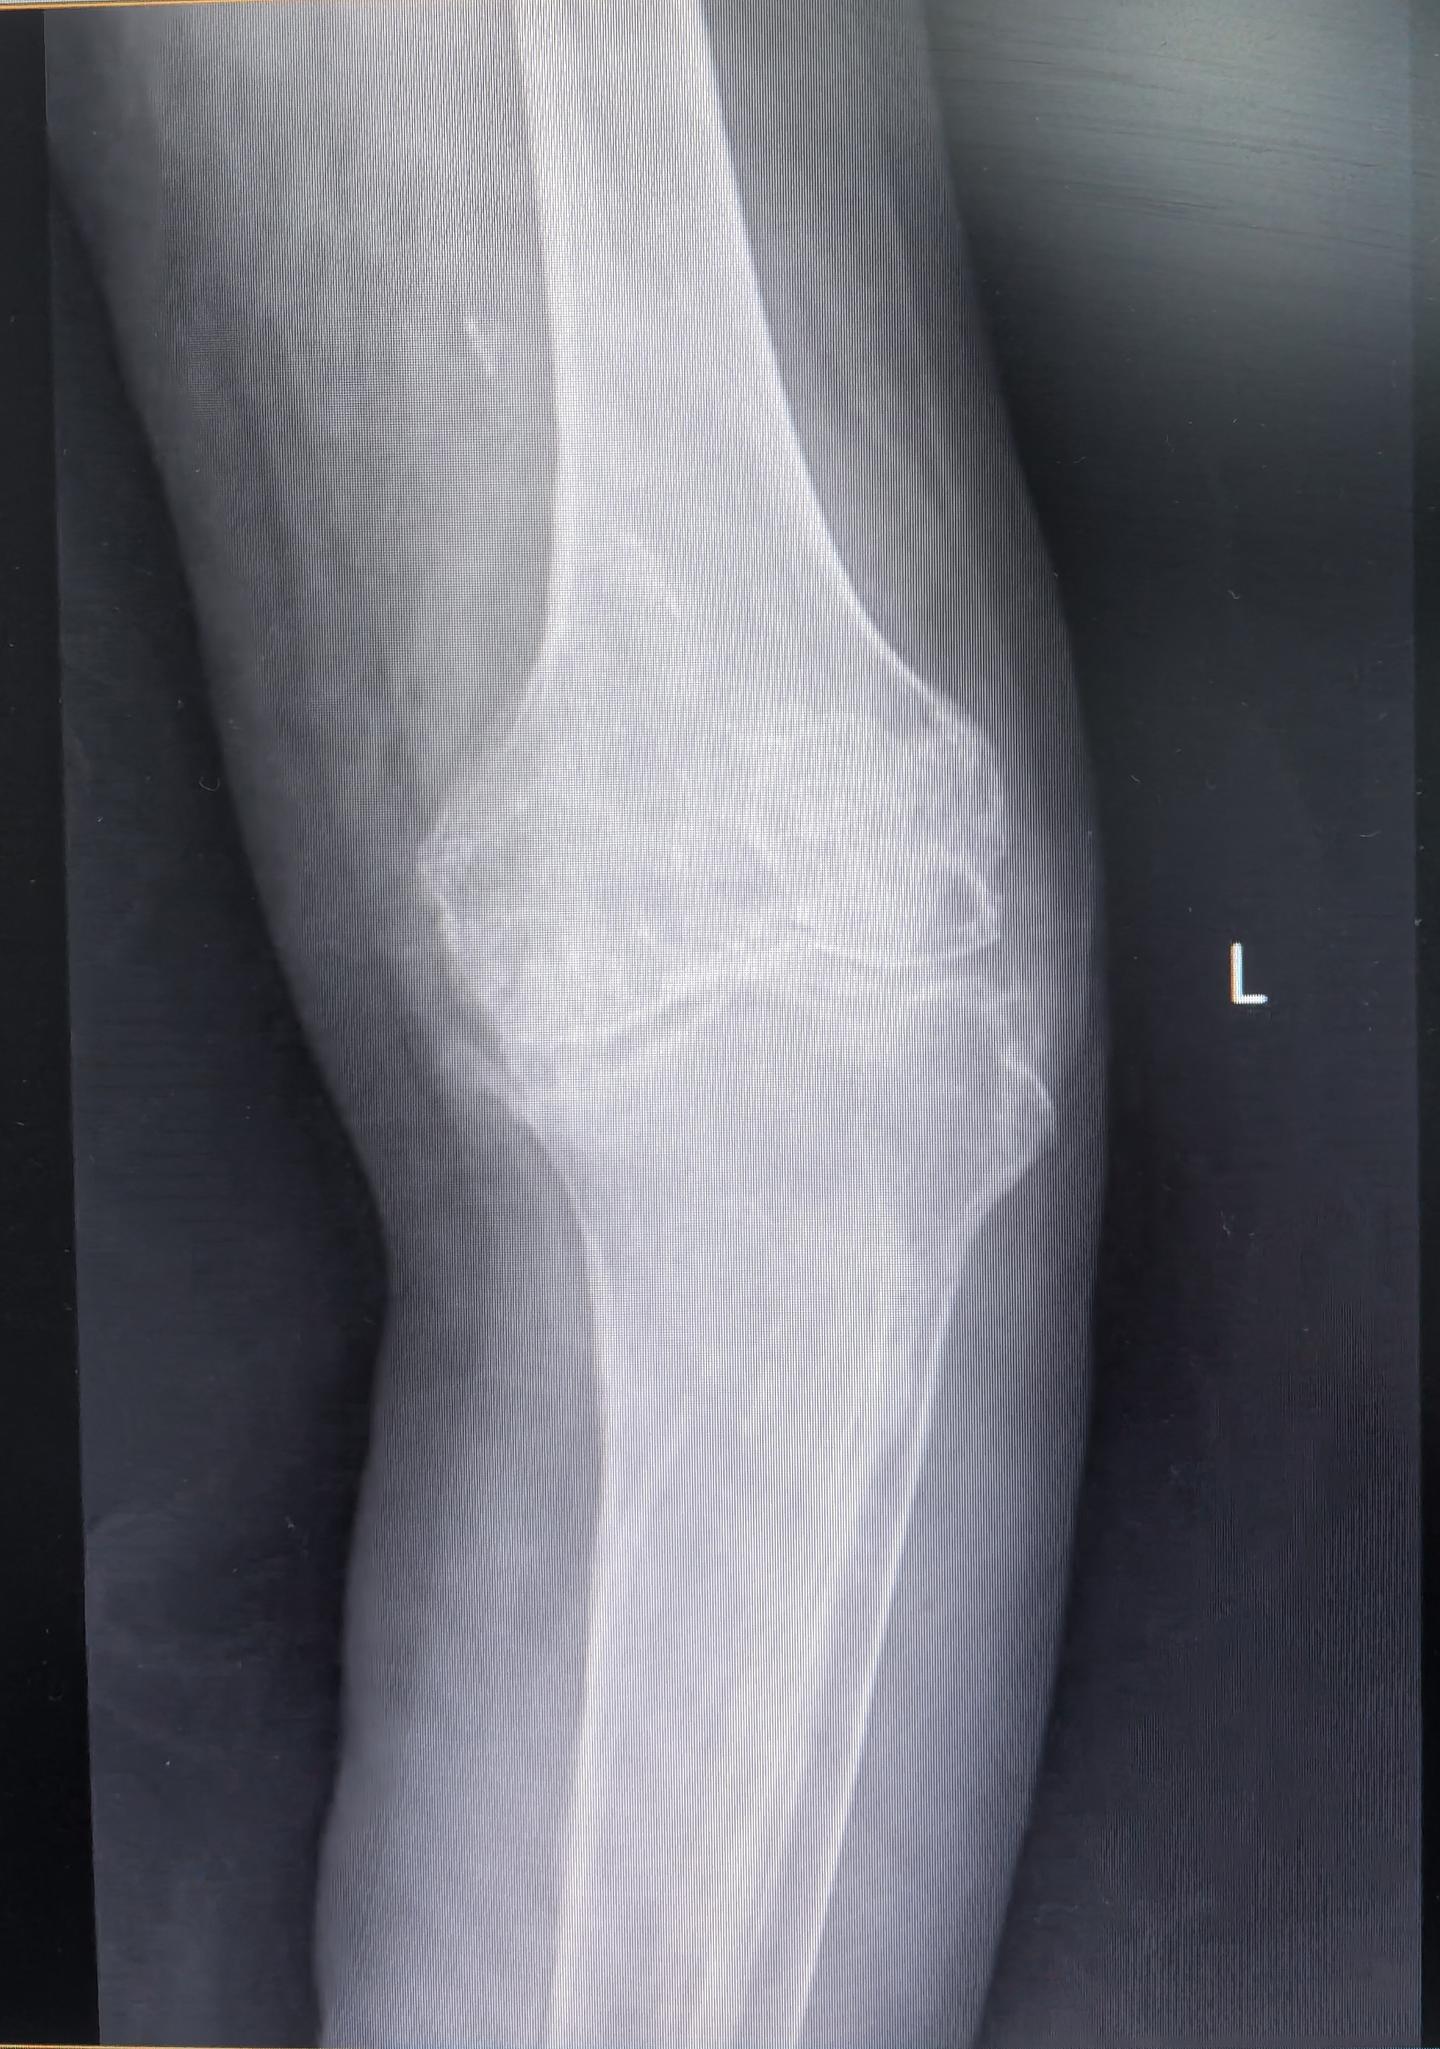

膝关节置换TKA.受罪多年的85岁老爷子,终于下定了决心。其实骨性关节炎到了这种地步,伸不直蜷不住,走路都困难,真是早做早受益。